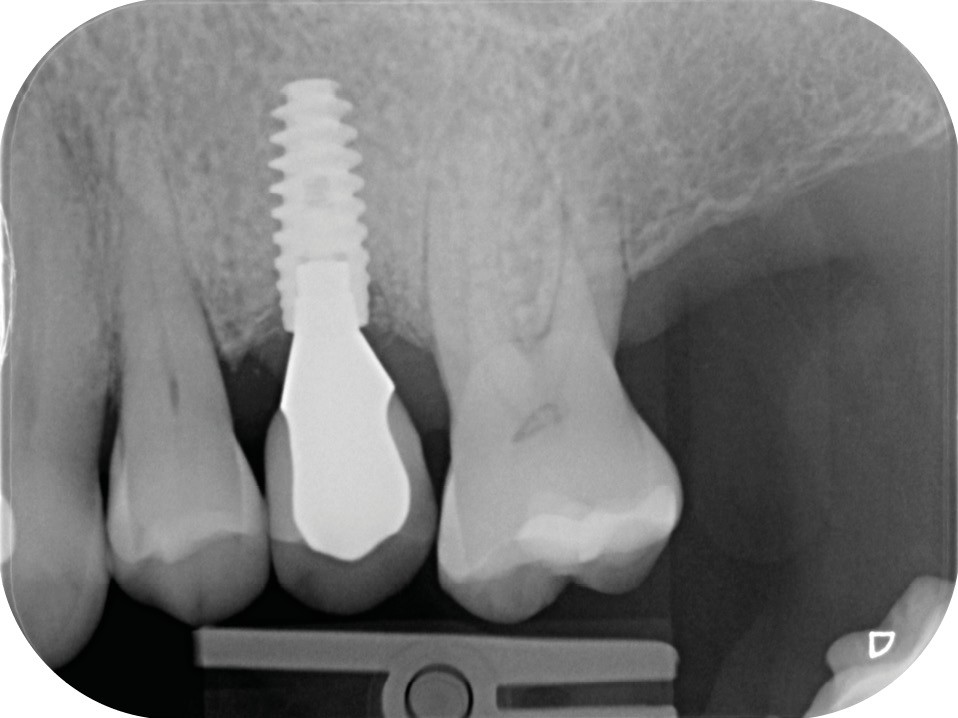

13 et 14. À 3 ans, une régénération osseuse satisfaisante et un bel aspect des tissus péri-implantaires sont observés. Les poches font 3 mm en mésial, distal et palatin, et 2 mm en vestibulaire. Il n’y a pas de saignement au sondage.